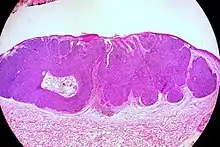

Micrograph of a basal-cell carcinoma, showing the characteristic histomorphologic features (peripheral palisading, myxoid stroma, artefactual clefting). H&E stain

Basal-cell carcinomas are currently considered to have origin from the folliculo-sebaceous-apocrine germ, also known as trichoblast. The differential diagnosis with trichoblastic carcinoma, a rare malignant form of trichoblastoma, can be challenging.[9] Alternatively, one argument is that basal-cell carcinoma is trichoblastic carcinoma.[10] Overexposure to sun leads to the formation of thymine dimers, a form of DNA damage. While DNA repair removes most UV-induced damage, not all crosslinks are excised. There is, therefore, cumulative DNA damage leading to mutations. Apart from the mutagenesis, overexposure to sunlight depresses the local immune system, possibly decreasing immune surveillance for new tumor cells.

Nodular basal-cell carcinoma (also known as "classic basal-cell carcinoma") accounts for between 50% and 80% of all BCC.[2] It most commonly occurs on the sun-exposed areas of the head and neck.[2] Histopathology shows aggregates of basaloid cells with well-defined borders, showing a peripheral palisading of cells and one or more typical clefts.[17] Such clefts are caused by shrinkage of mucin during tissue fixation and staining.[18] Central necrosis with eosinophilic, granular features may be also present, as well as mucin. The heavy aggregates of mucin determine a cystic structure. Calcification may be also present, especially in long-standing lesions.[17] Mitotic activity is usually not so evident, but a high mitotic rate may be present in more aggressive lesions.[17] Adenoidal BCC can be classified as a variant of NBCC, characterized by basaloid cells with a reticulated configuration extending into the dermis.[17]